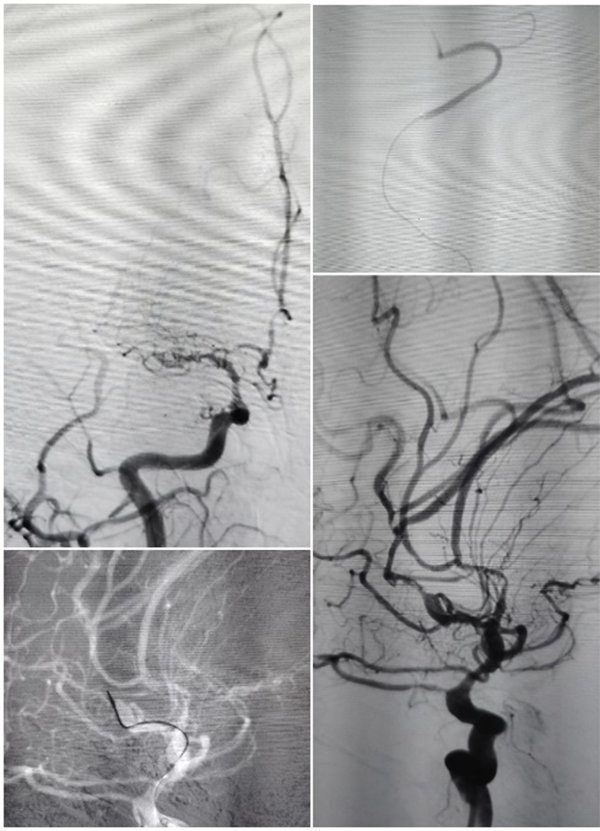

随着时间的推移,一例例复杂的全麻手术被成功完成:

青年卒中患者

全麻下大脑中动脉亚急性期闭塞再通术

高龄患者前交通不规则动脉瘤

全麻下支架辅助弹簧圈栓塞术

让我印象深刻的是位39岁的年轻男性患者,突发头晕伴右侧肢体麻木无力、言语不利,脑血管造影显示:椎动脉颅内段血管闭塞。患者病情复杂,血管闭塞节段长,而且血管条件差,开通闭塞血管的手术风险也相应增加,但如果选择保守治疗,将来发生严重卒中的风险非常高。

张主任带领团队对患者病情进行了细致分析,制定了详细的手术方案及预案,手术仅耗时40余分钟,夜里23:40,手术圆满结束。